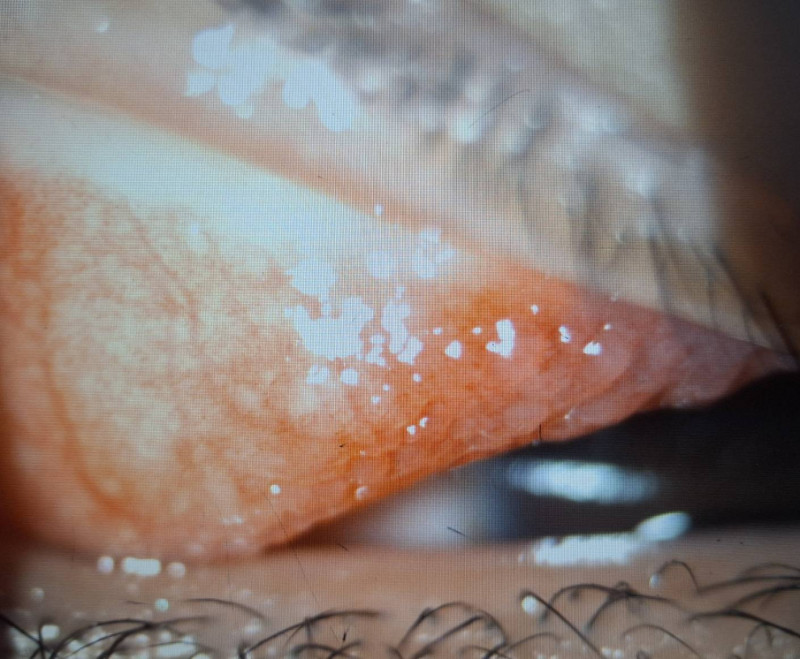

小二男童因長期眼睛癢揉眼,結膜炎導致左上眼瞼出現多顆巨大乳突。(洪啟庭提供)

〔記者許麗娟/高雄報導〕1名國小二年級男童近半年來常覺得左眼非常癢而不斷眨眼、揉眼,近日左眼眼瞼嚴重腫脹家長帶他就醫,檢查發現上眼瞼結膜充血外,還長了許多巨大的疙瘩物,每顆直徑都大於0.1 公分,並覆蓋白色黏液,診斷為「巨大乳突結膜炎合併角膜潰瘍」,醫師提醒,孩童若不斷眨眼就應儘快就醫檢查。

達特楊眼科聯盟執行長洪啟庭指出,小二男童就醫時不僅左眼眼瞼嚴重腫脹,最佳視力僅0.5並有300度散光,應是過敏性結膜炎合併過敏性鼻炎、濕疹、異位性皮膚炎或氣喘等,因為長期揉眼導致眼皮長滿巨大乳突,因長時間壓迫造成上半部角膜有淺層潰瘍,故造成300度的高度散光和視力模糊,經強效抗生素與適當類固醇藥水治療,2星期後角膜潰瘍痊癒,乳突的也變小,學童眨眼睛的現象也明顯改善,但乳突完全消失恐要半年以上。